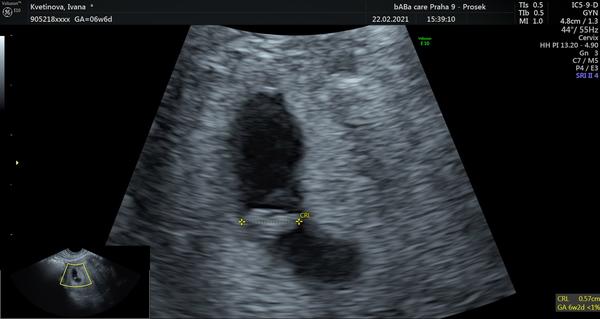

Návštěva gynekologa. Bude v 6+0 už srdíčko?

Ahoj holky, mám dotaz zítra jdu na první kontrolu v 6+0 myslíte, že už bude srdíčko?

Záleží, jestli je to opravdu 4 týdny od ovulace. Třeba když jsem byla dle ms 6+0, tak reálně jsem byla těhotná o 10 dní méně (pozdní ovulace). Nicméně 6+0 dle ovulace už tam srdíčko blikalo

To je docela brzo... ja mela v 6+3 gestacni vacky a srdicka byly a bily az o tyden pozdeji.